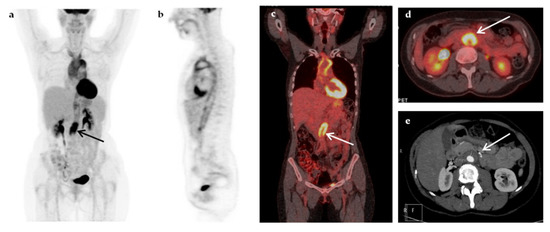

| Malignancy | 8 (16%) |

| Non-Hodgkin’s lymphoma | 5 |

| Hodgkin’s disease | 1 |